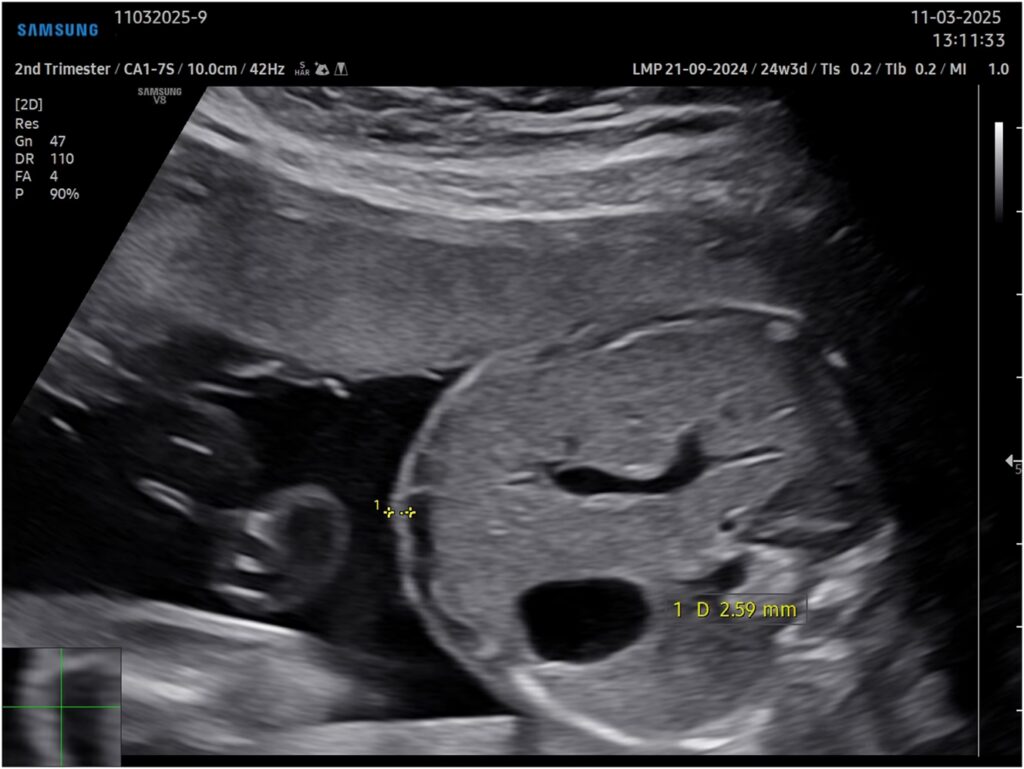

Parallelt med den øgede adgang til forskning er der et voksende fokus på vigtigheden af prænatal rådgivning, især når scanninger afslører potentielle anomalier hos fosteret. At modtage en sådan nyhed kan være overvældende for vordende forældre. Her spiller specialiseret rådgivning, ofte ledet af en pædiatrisk kirurg eller en anden specialist, en afgørende rolle. Formålet er ikke blot at informere, men at oversætte kompleks medicinsk information til et klart og forståeligt sprog, der giver forældrene handlekraft.

En undersøgelse har vist en bemærkelsesværdig høj korrelation på 87,4% mellem den diagnose, der stilles prænatalt (før fødslen) gennem avanceret føtodiagnostik, og den endelige diagnose efter fødslen. Denne præcision er fundamentet for meningsfuld rådgivning. Når forældre møder en specialist, får de et detaljeret billede af:

- Føtale Anomalier: Forbedrede ultralydsteknikker og diagnostiske kriterier.

Hvad betyder en korrelation på 87,4% mellem prænatal og postnatal diagnose?

Det betyder, at i næsten 9 ud af 10 tilfælde er den diagnose, som specialister stiller ved hjælp af f.eks. ultralydsscanning før fødslen, den samme som den, der bekræftes efter barnet er født. Denne høje nøjagtighed gør den prænatale rådgivning yderst pålidelig og værdifuld.